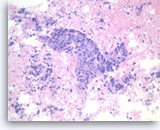

Adenocarcinoma, poorly differentiated,

Pancreas FNA, Cell Block.

Large pleomorphic tumor cells are present singly or in small stratified groups with irregular glandular lumina. Necrosis is present.

40X